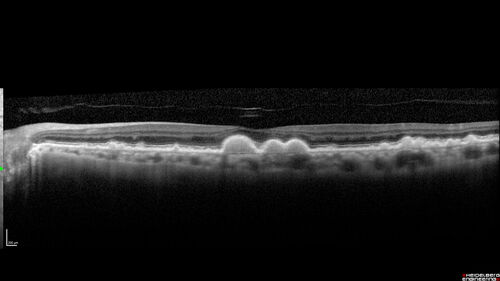

Intermediate Dry Age-Related Macular Degeneration - Soft Drusen

70-year-old Left eye worse than the right.  Both eyes see distortion in the amsler grid for a few months

HTN, High Lipids, Osteoporosis

Meds: Lutein once daily, Calcium, Fish oil, Red Yeast Rice, CoQ10, Magnesium, MVI, Xanax

VA 20/16 OU

2+NS cataract